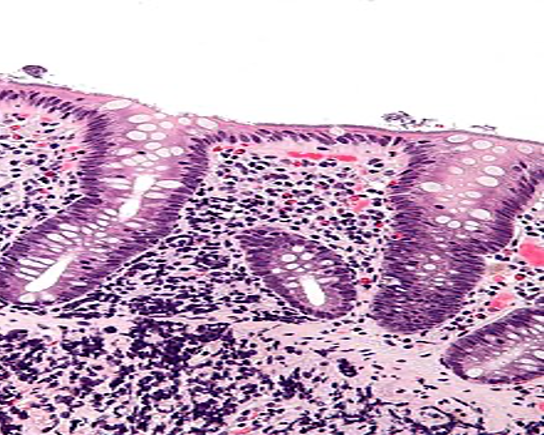

HISTOPATHOLOGY

Fig shows an endoscopic biopsy from a 54 year old individual. Identify the anatomical part of the intestine. What is the pathology. With what clinical symptoms do these patients present? (see surface epithelium)